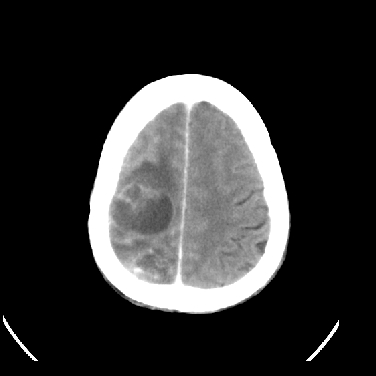

男,45岁,左侧肢体乏力1周。ex:胸片示:两肺团块状、斑片状密度增高影,其内可见小空洞。支纤镜、经皮肺穿示:干酪样物。

结合病史考虑结核性脑炎脑膜炎,伴脑脓肿形成

考虑右侧顶叶脑脓肿形成。

同意“考虑结核性脑炎脑膜炎,伴脑脓肿形成”的意见,不轻易怀疑肿瘤。

考虑结核性脑炎脑膜炎,伴脑脓肿形成。

考虑右侧顶叶脑脓肿(结核性?)。

结核性脑脓肿可能大

结合病史考虑结核性脑炎脑膜炎,伴脑脓肿形成,囊变转移瘤不除外